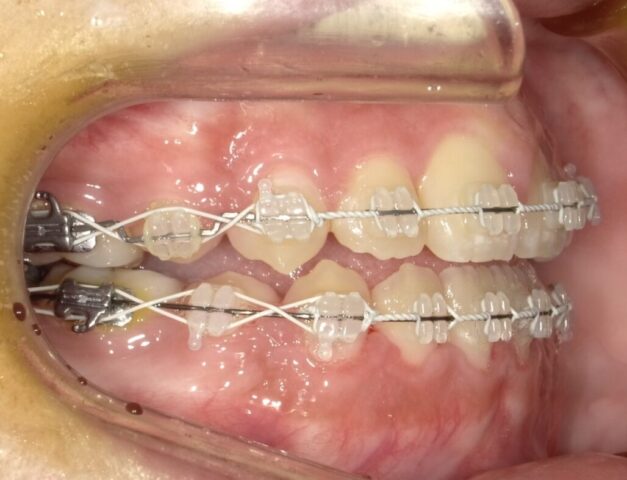

≪左側面観≫

2023年5月

2023年6月

2023年7月

2023年8月

2023年9月

2023年10月

2023年11月

2023年12月

2024年1月

2024年2月

2024年3月

2024年4月

2024年5月

2024年6月

2024年7月

2024年8月

2024年9月

2024年10月

2024年12月

2025年1月